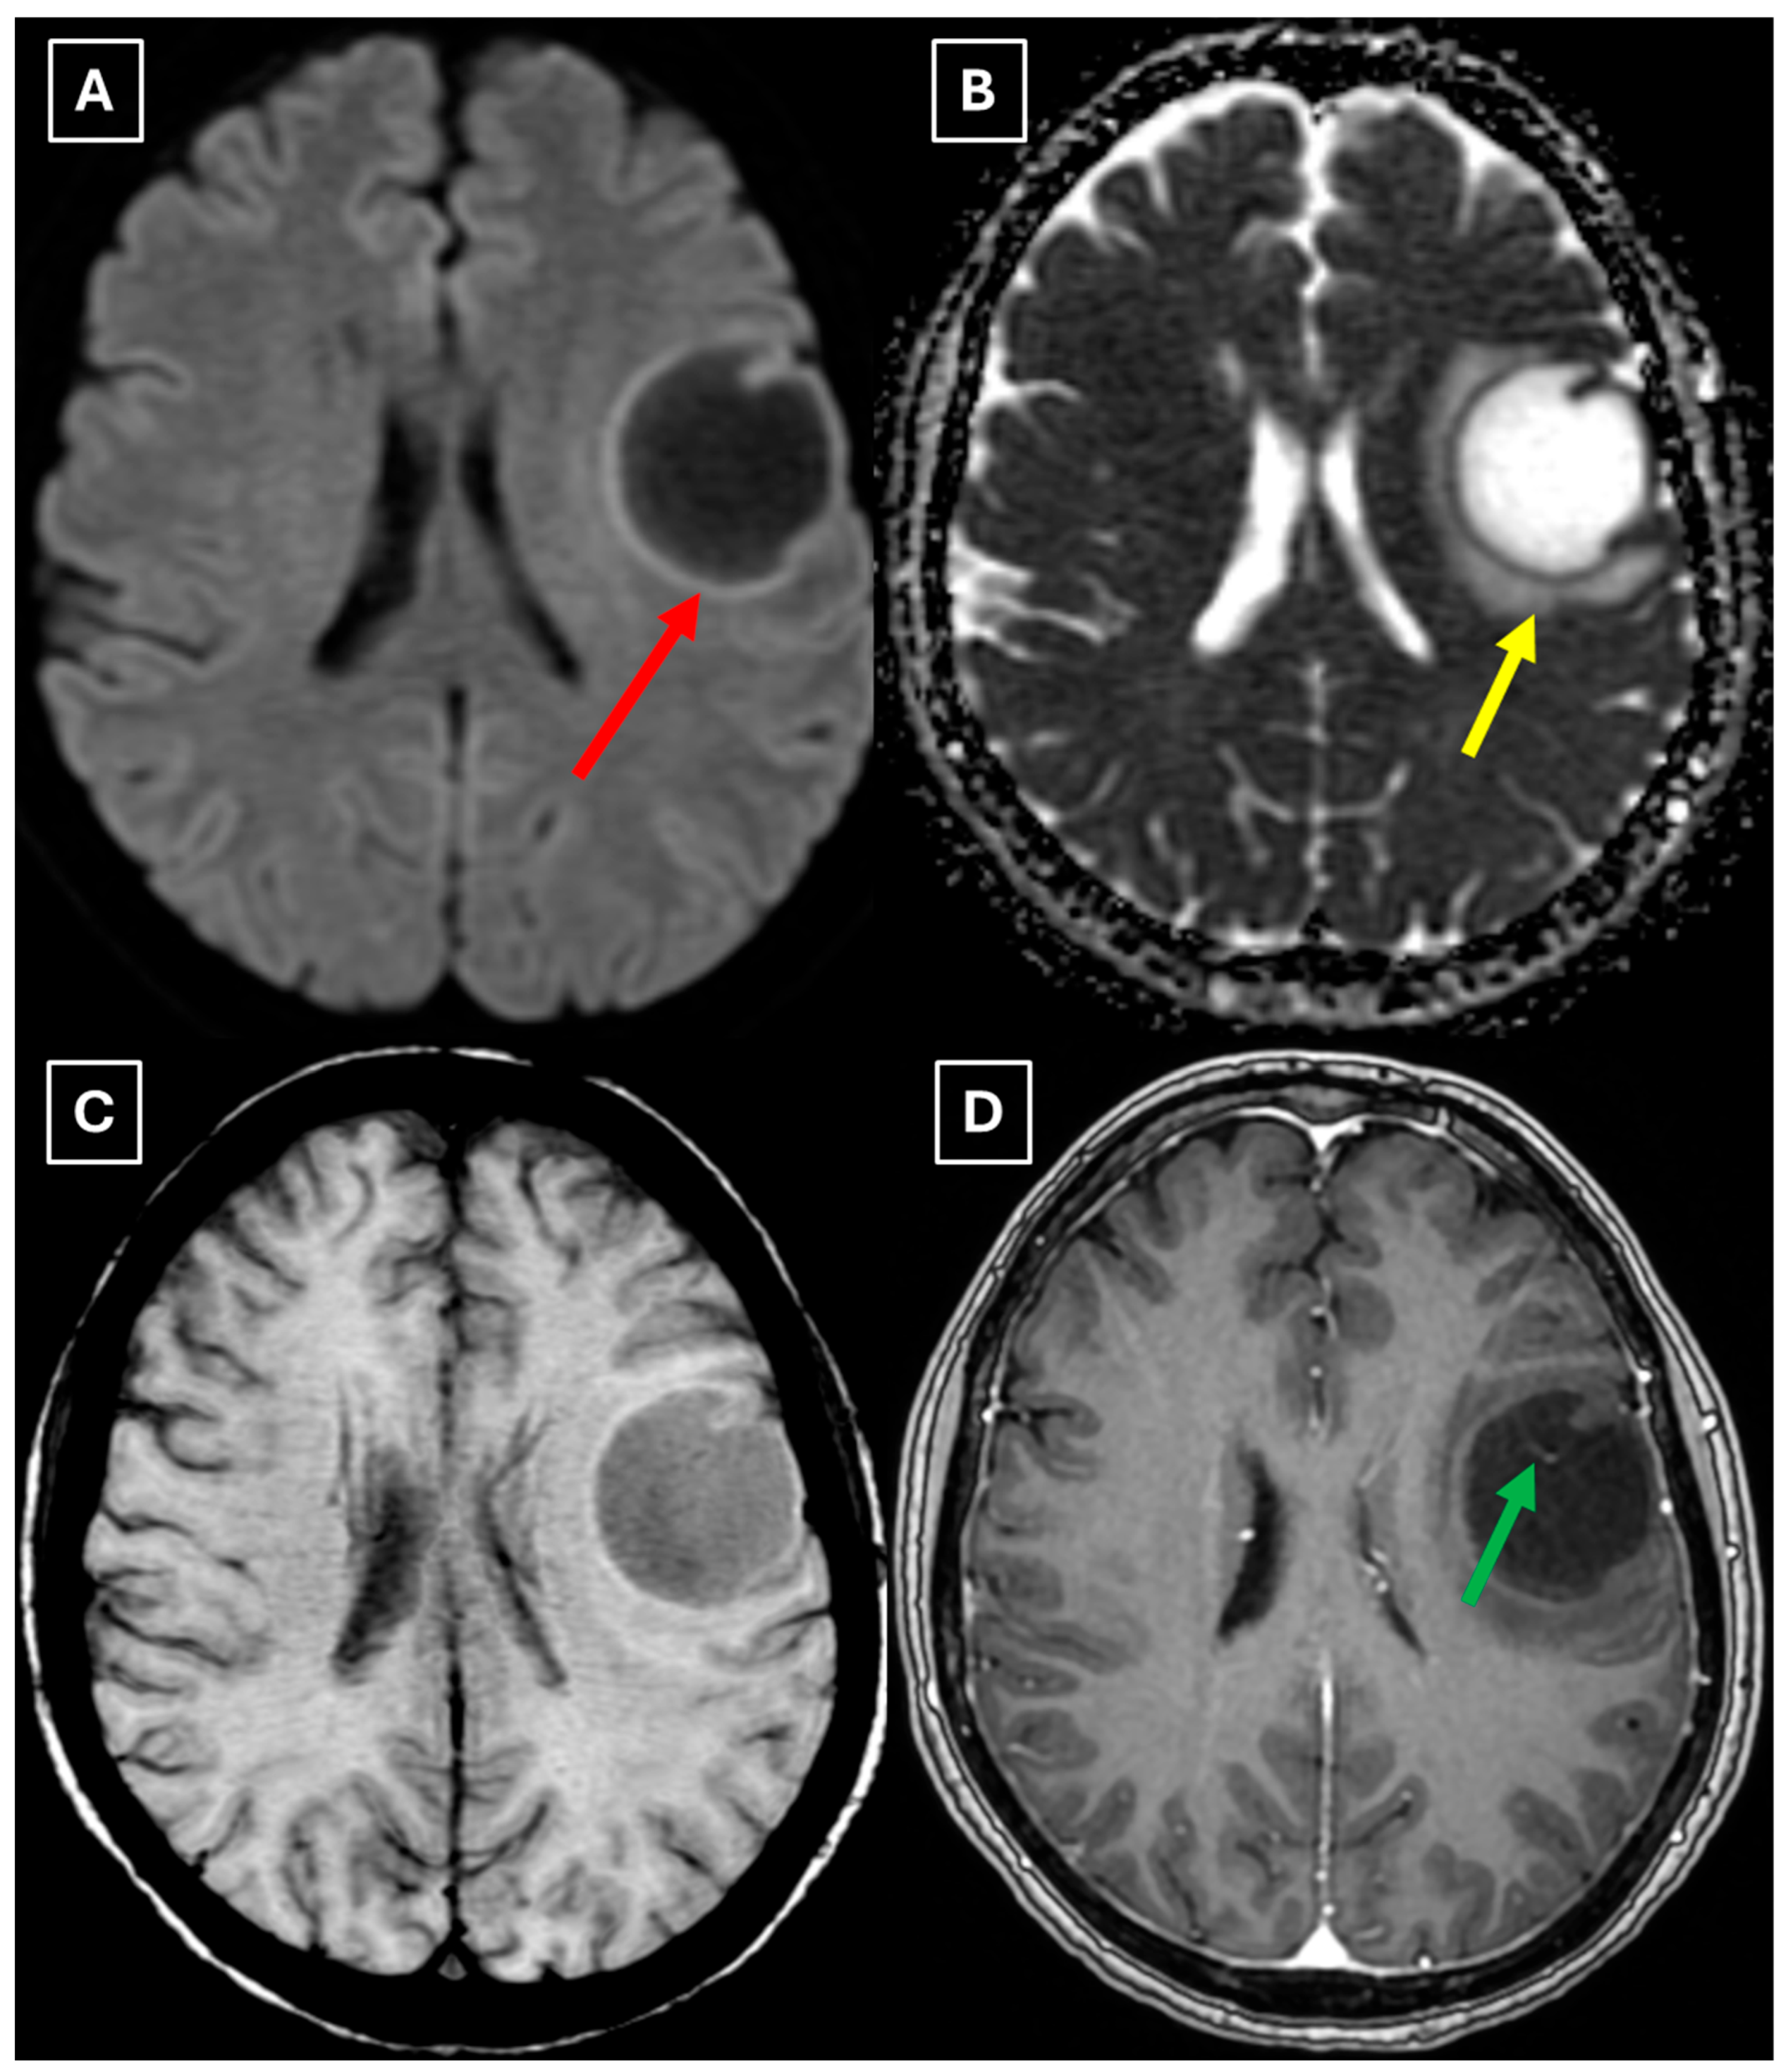

Figure 1. Native head CT without I/V contrast Images (A,B) show a. Hypodense lesion in the left hemisphere, basal parts of the frontal lobe. Measuring up to at least 3.5 cm in maximum size, with mild perifocal edema. Red arrow—indistinct formation.

One week later, a brain MRI with intravenous contrast was performed, which revealed a well-defined subcortical lesion approximately 3.5 cm in diameter in the posterior basal parts of the left frontal lobe, accompanied by perifocal edema and sulcal effacement (Figure 2). No pathological contrast enhancement was observed (Figure 3). No other white matter lesion was identified to suggest signs of leukodystrophy, and no hemosiderin deposits were identified in the brain or meninges (Figure 3). Given the T2/FLAIR mismatch (Figure 2), the most likely diagnosis was infiltrative low-grade astrocytoma. The patient received mannitol anti-edema therapy, resulting in clinical improvement and a reduction in neurological symptoms. The case was discussed by a multidisciplinary team (neurologist, neurosurgeon, radiologist, oncologist, and pathologist). Surgical treatment and morphological verification of the tumor were recommended. A day later the patient was discharged from the hospital in a stable condition, with a recommendation to be admitted to the neurosurgery department for surgery in two weeks. She was prescribed dexamethasone tablets of 0.5 mg twice daily on an outpatient basis.

Figure 2. MRI scan of the brain. (A): Axial T2-weighted sequence shows a well-defined, homogenous, hyperintense mass-like lesion in the inferior part of the left frontal lobe, with involvement of the juxtacortical white matter and relative sparing of the cortical gray matter. The lesion measured 37.34 mm × 34.85 mm (AP × LL). Additionally, there is incomplete perifocal edema surrounding the lesion, extending to the white matter and away from the cortex. (B): Axial FLAIR sequence shows the lesion with a relatively more hypointense center and a hyperintense peripheral rim at the lesion margins. A T2/FLAIR mismatch sign was observed, making the likely diagnosis an infiltrative low-grade astrocytoma. All MRI images were acquired with the Philips “Ingenia Ambition X” 1.5T system. Red arrow—indistinct formation, yellow arrow—perifocal vasogenic edema.

Figure 3. MRI scan of the brain. (A): Axial trace image of diffusion-weighted imaging (DWI) shows slight diffusion restriction in the lesion wall when correlated with (B): dark signal on apparent diffusion coefficient (ADC) maps in the wall of the lesion, with no central diffusion reduction observed. (C): In the corresponding axial slice of the susceptibility-weighted imaging (SWI) sequence, there is no evidence of blood products within the lesion. (D): On the axial postcontrast T1-weighted imaging, there is no contrast enhancement in the lesion, although a central vein-like structure is observed. Red arrow—diffusion restriction, yellow arrow—perifocal vasogenic edema, green arrow—central vein sign.

Finally, we provide a high-resolution MRI follow-up of two months’ duration showing near-complete regression of the lesion after corticosteroid therapy. The lesion decreased from 37.34 mm × 34.85 mm (AP × LL) to 24.87 mm × 29.71 mm following two weeks of corticosteroid therapy and after almost two months from the first MRI scan to minimal patchy contrast enhancement (Figure 7D). This marked decrease in the size of the lesion gives strong evidence that a demyelinating rather than neoplastic process is present.

There are no pathognomonic features for tumefactive demyelinating lesions, but there are still some MRI findings that support the diagnosis. TDLs appear larger than 2 cm and are most often located in the frontal or parietal regions. The supratentorial white matter, especially in subcortical and periventricular locations, is commonly affected. On T1-weighted images they usually demonstrate hypointensity and hyperintensity on T2-weighted images, consistent with demyelination. These lesions have a varying degree of perifocal edema and mass effect, but both are usually mild relative to the lesion size in comparison to neoplasms or abscesses. The most characteristic enhancement pattern is the open-ring (incomplete rim) enhancement, which is significantly more common in TDLs than closed-ring enhancement. The open ring typically faces the cortex or gray matter and is considered a strong supportive feature for TDL diagnosis [3,11,18]. Contrast enhancement is not a universal feature, as Lucchinetti et al. (2008) [1] reported that approximately 5% of TDLs on postcontrast T1-weighted MRI did not show enhancement in their study. This finding was also observed in this case (Figure 3D), as well as in the case presented by Zafar et al. (2022) [19]. Therefore, the absence of enhancement does not necessarily exclude a demyelinating pathology.

Another MRI feature strongly associated with TDLs is a central vein sign (CVS), which was also observed in this case (Figure 3, Figure 5, and Figure 7), currently being considered for inclusion in MS diagnostic criteria. On SWI or T2-weighted sequences, CVS appears as a thin hypointense line or dot less than 2 mm in diameter, visible in at least two planes, and running partially or completely through the center of a lesion [2]. Although most studies of the CVS have focused on MS and radiologically isolated syndrome, the CVS is also applicable for TDLs, representing an atypical variant of MS. In radiologically isolated syndrome, Suthiphosuwan et al. (2019) [21] reported a median of 87% CVS-positive lesions per case, underscoring its strong association with inflammatory demyelination [2]. In the TDL cohort described by Ongphichetmetha et al. (2024) [2], CVS was observed in approximately half of the patients, while open-ring enhancement occurred at a similar frequency of around 50%, with both features supporting an inflammatory demyelinating rather than neoplastic process.

We also found similarities between this case and the classical imaging features of TDLs described in the literature. Hypoattenuation on noncontrast CT corresponding to enhancing areas on MRI is another useful imaging finding in TDLs [10], which may be explained by the tissue rarefaction caused by the active demyelination rather than increased cellularity, which is seen in tumors, thereby supporting the use of MRI with noncontrast CT in TDL diagnosis. Furthermore, restricted diffusion along the lesion margin with elevated central ADC values, in contrast to neoplasms which more commonly show central diffusion restriction, have been described as a commonly presenting feature of TDLs [3,4,10], which was also observed in this case (Figure 5A,B).

In this case, despite the presence of a T2/FLAIR mismatch sign (Figure 2), several imaging characteristics were more suggestive of a TDL rather than IDH-mutant astrocytoma. The lesion was located in juxtacortical white matter and had cortical sparing, which is unusual for IDH-mutant astrocytomas, since they typically have been shown to infiltrate and expand the cortex. The diffusion restriction at the lesion margin with centrally elevated ADC values was more consistent with reported DWI findings of TDLs and contrasted with the central restriction often seen in gliomas. The mass effect was mild in comparison to the overall lesion size, favoring demyelination rather than neoplasm in this case. Additionally, the lesion had a central vein sign, as described above, a radiological sign supportive of inflammatory demyelination. The combination of cortical sparing, peripheral diffusion restriction, mild mass effect, and the appearance of central vein sign represented strong features that raised suspicion of a tumefactive demyelination lesion.